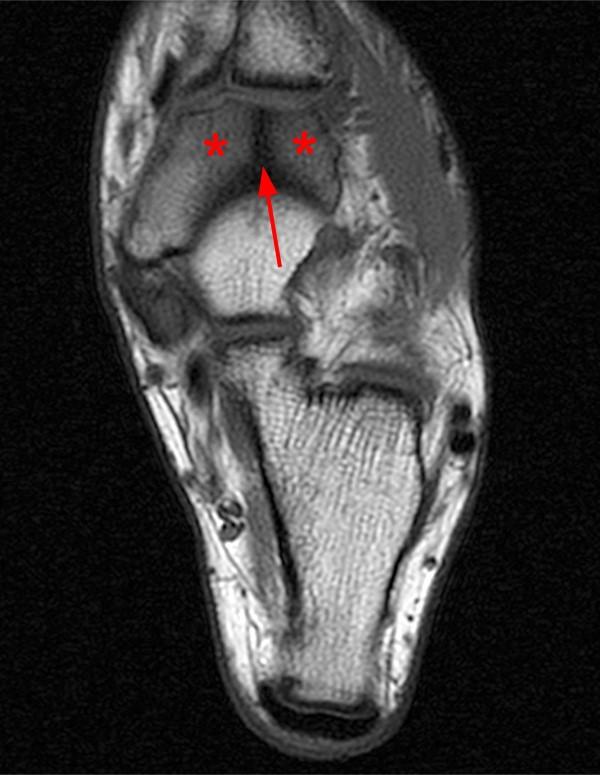

Fossa

•shallow, basin-like depression in a bone, often serving as an articular surface

•fossil sits in

Condyle

•rounded articular projection; often articulates with a corresponding fossa

•rounded connector